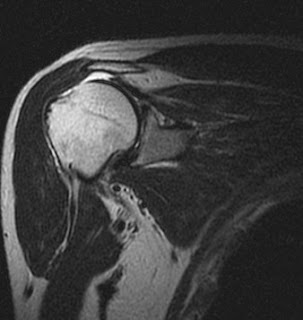

This is a chest CT image of a young male with fever, recurrent cough. CT chest shows well defined area in left lower lobe with cystic comp...